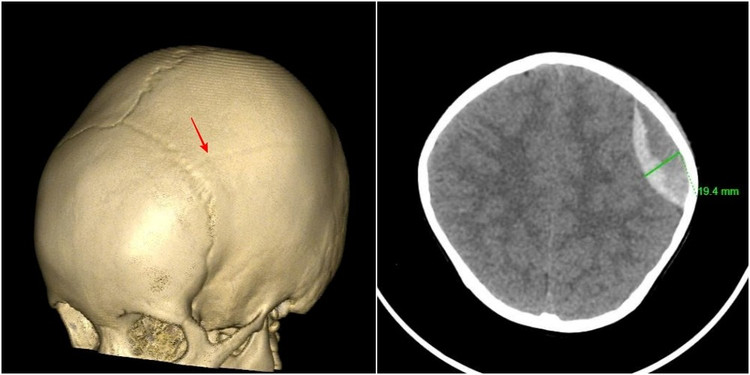

Hình ảnh vỡ xương sọ, tụ máu ngoài màng cứng đỉnh trái của bệnh nhi 3 tuổi - Ảnh BVCC

Kết quả chụp cắt lớp vi tính cho thấy hình ảnh vỡ xương sọ, chảy máu ngoài màng cứng đỉnh trái. Các bác sĩ chẩn đoán bệnh nhi bị chấn thương sọ não do ngã, vỡ xương, tụ máu ngoài màng cứng đỉnh trái.